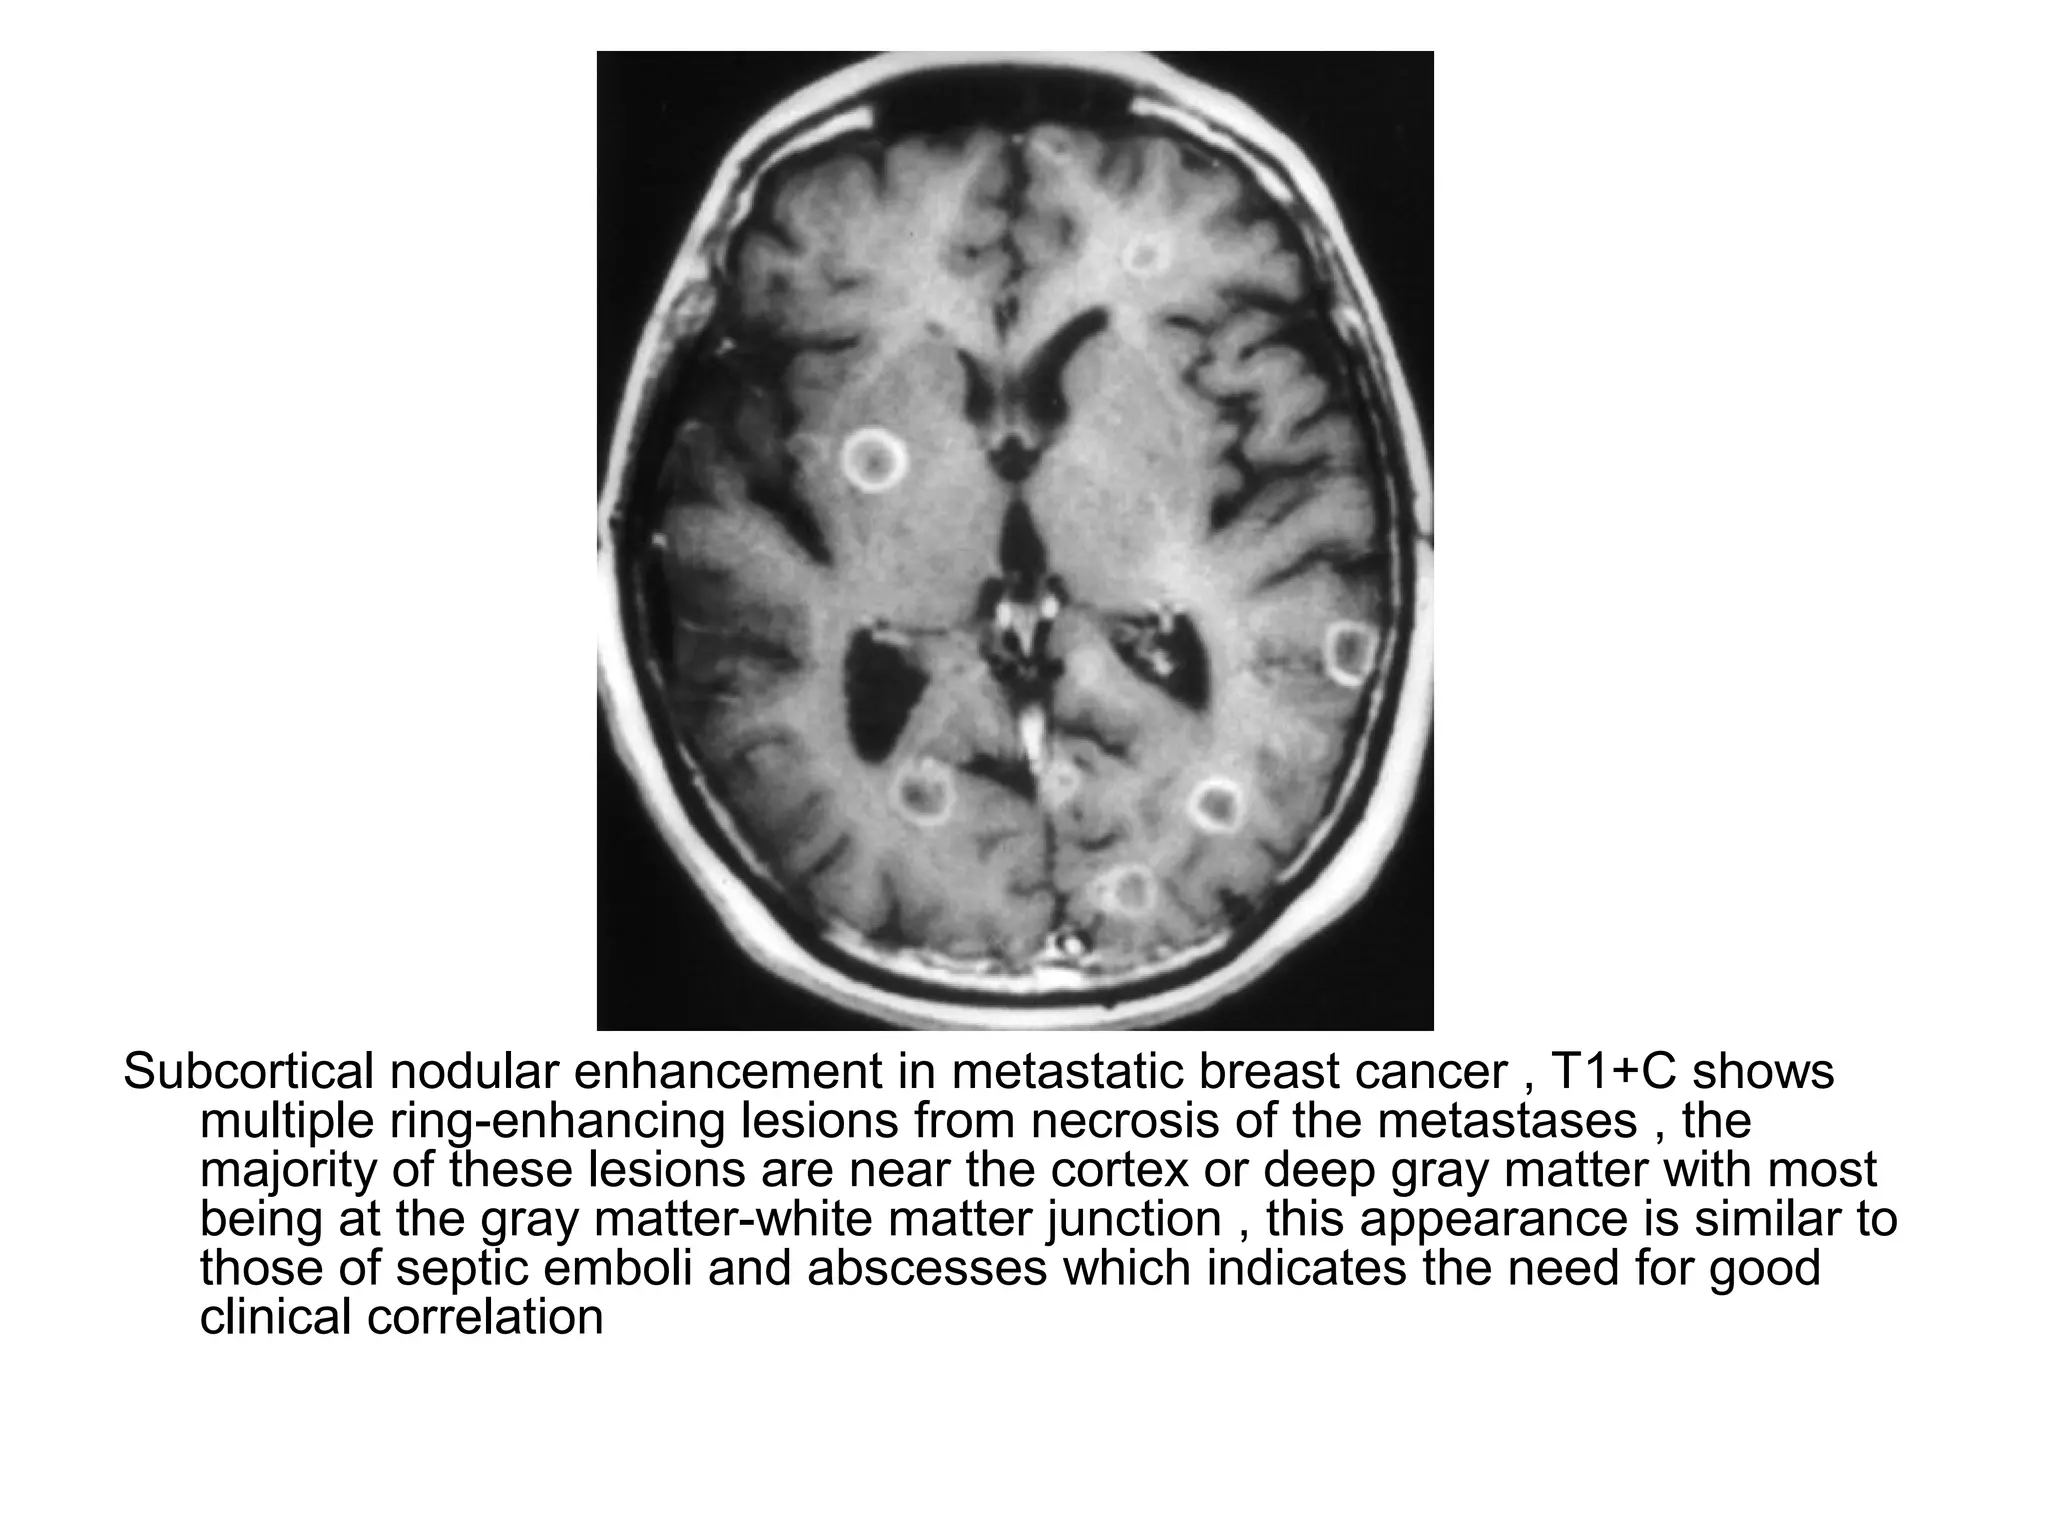

Subcortical nodular enhancement in metastatic breast cancer , T1+C shows

multiple ring-enhancing lesions from necrosis of the metastases , the

majority of these lesions are near the cortex or deep gray matter with most

being at the gray matter-white matter junction , this appearance is similar to

those of septic emboli and abscesses which indicates the need for good

clinical correlation